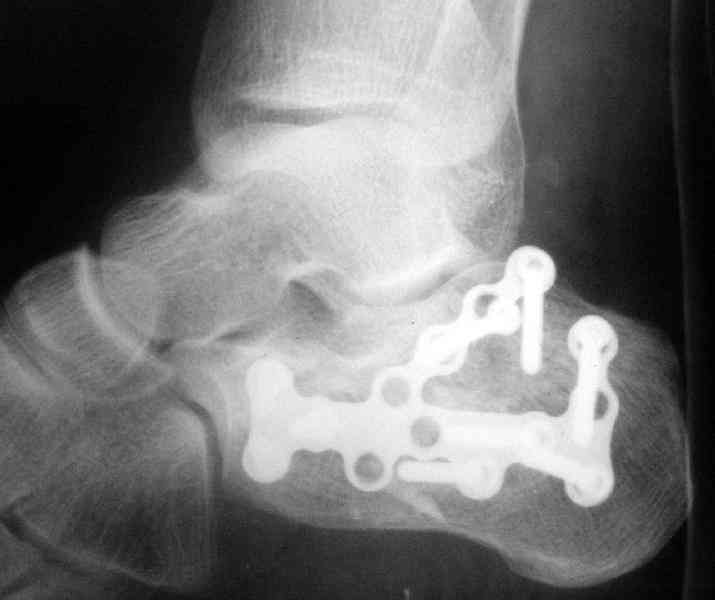

MOST OF MY COLLEGUES WOULD OPEN IT LATERALLY( a flap) and having a proper reduction would put a plate.

Имея какой-то опыт остесинтеза пяточной кости пластинами пришли к выводу - где есть альтернатива лучше без нее, где нет значит пластина и долгие переживания в ожидании очередной перевязки. Может нам так не везло, но и одного некроза( слава богу без остеомеилита) достаточно, чтобы призадуматься.